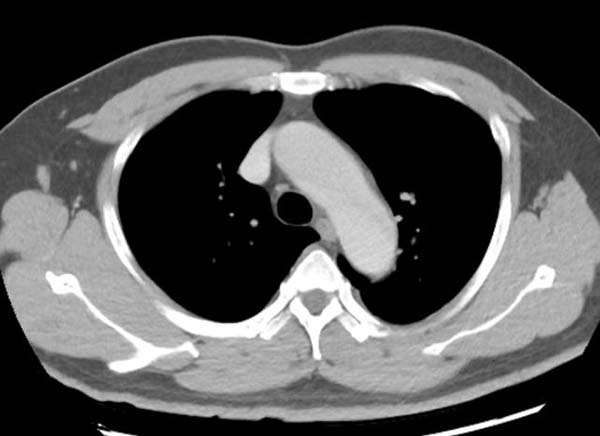

在应用间接法-智能追踪扫描方式时,如果留置针位置选择不当,可能会出现大部分对比剂未能第一时间参与灌注,导致在肺循环中对比剂与血液比例远低于正常值,即便达到靶血管的阈值,而感兴趣区CT值仍然过低,影响诊断。

灌注不足 主动脉弓CT值过低